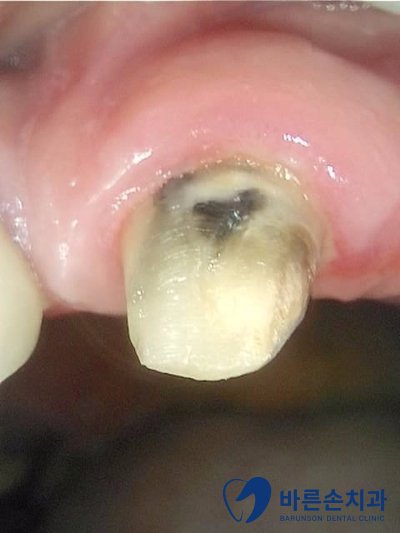

브릿지가 빠져있고 남아있는 치아를 보니 연결해서 쓰던 치아 내부에 2차 충치가 생겼습니다.

사실 상태가 좋지 않아 발치 가능성이 높았지만 최대한 자연 치아를 살려보고자 치료를 들어갔어요 ‘-‘

크라운은 임플란트에 비해 빠른 치료가 가능해서

바로 본 뜨고 보철제작에 들어가요~!